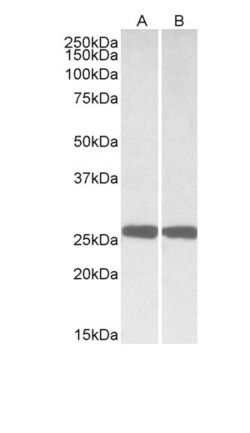

PGP9.5 (Protein gene product 9.5, UCH-L1, PARK5) is a neuron specific protein, structurally and immunologically distinct from neuron specific enolase. PGP9.5 has a molecular weight of 27 kDa and was first identified by high resolution two dimensional PAGE. PGP9.5 is a member of ubiquitin carboxyl-terminal hydrolase family 1 (peptidase family C12) with a ubiquitin carboxyl-terminal hydrolase domain. PGP9.5 is well known for having ubiquitin hydrolase and ligase activities that hydrolyzes small C-terminal adducts of ubiquitin to generate ubiquitin monomers. PGP9.5 is present in neurons and nerve fibers at all levels of the central and peripheral nervous system, in neuroendocrine cells, in segments of the renal tubules, in spermatogonia and Leydig cells of the testis, in ova and in some cells of both the pregnant and non-pregnant corpus luteum. Over expression of PGP9.5 leads to non-small cell lung cancer while decreased expression leads to Huntington disease and Alzheimer disease. Since PGP9.5 is present in cellular inclusions, it can be a useful as a neuronal marker and in the studies of neurodegenerative disorders such as with Parkinson disease.

| Immunohistochemistry (Paraffin), Western Blot, Western Blot | |